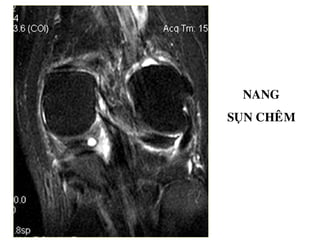

NANG

SUÏN CHEÂM